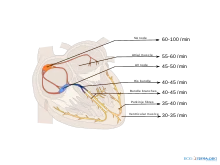

Pacemakers

The heart has several pacemakers, each which fires at its own intrinsic rate:

- SA node: 60–100 bpm

- Atrioventricular node(AVN): 40–60 bpm

- Purkinje fibres: 20–40 bpm

The potentials will normally travel in order

SA node → Atrioventricular node → Purkinje fibres

Normally, all the foci will end up firing at the SA node rate, not their intrinsic rate in a phenomenon known as overdrive-suppression. Thus, in the normal, healthy heart, only the SA node intrinsic rate is observable.

However, in pathological conditions, the intrinsic rate becomes apparent. Consider a heart attack which damages the region of the heart between the SA node and the AV node.

SA node → |block| AV node → Purkinje fibres

The other foci will not see the SA node firing; however, they will see the atrial foci. The heart will now beat at the intrinsic rate of the AV node.